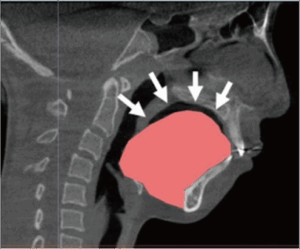

・母乳哺育の口腔機能影響

・舌の動きと下顎の成長

・人工乳首のタイプ(大きさ・形態・硬さ)による舌運動

・乳首の形状による1回の吸啜における舌運動の幅、持続時間